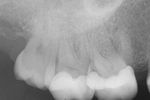

Durch die digitale Volumentomografie lassen sich wichtige zusätzliche diagnostische Informationlassen gewinnen. Die räumliche Darstellung erleichtert die Behandlungsplanung und gibt Sicherheit in der Therapie.

Die digitale Volumentomografie wird bei folgenden Verdachtsdiagnosen empfohlen:

– apikale Veränderungen bei Vorliegen klinischer Auffälligkeiten, wenn diese auf zweidimensionalen Aufnahmen nicht detektierbar bzw. räumlich korrelierbar sind

– Wurzelfrakturen, da diese aus rein mathematischen Gründen sicherer identifiziert werden als mit zweidimensionalen Aufnahmen

– Perforation, insbesondere Stiftperforationen

– dentales Trauma

– interne und externe Wurzelresorptionen

– erschwerte Begleitumstände wie komplexe Anatomie des Wurzelsystems

– Gefährdung anatomischer Nachbarstrukturen

– intrakanalär frakturierte Wurzelkanalinstrumente